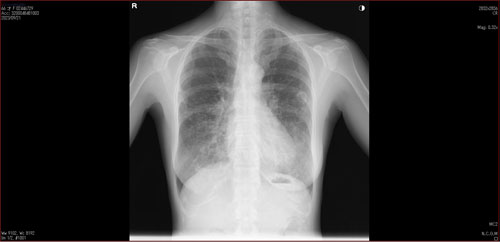

肺X線画像

- 2023.05.11 要観察と診断された画像(国立系病院)